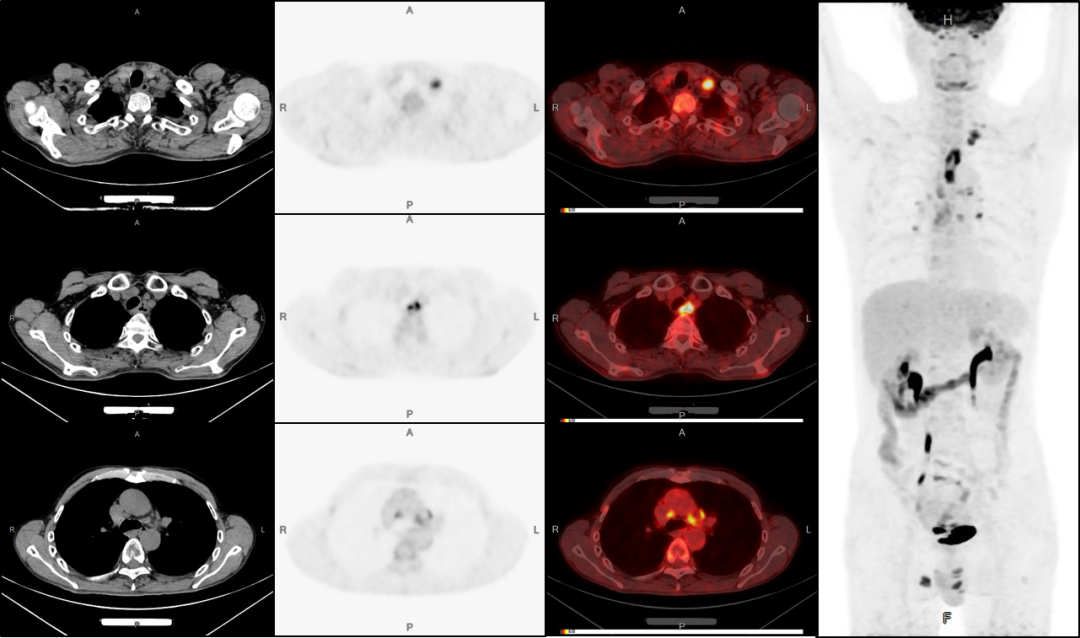

病例3:男性,72歲。結(jié)腸腺癌術(shù)后3年,右肺鱗癌術(shù)后1年隨訪。

4、肝脾多發(fā)轉(zhuǎn)移灶可能。